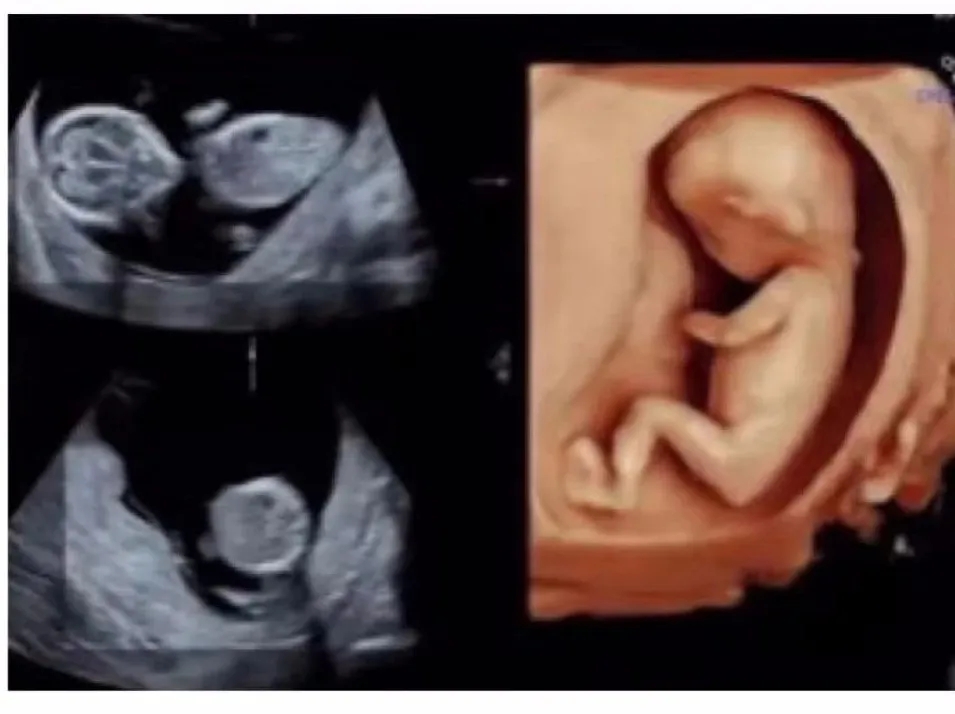

终于,到了李女士万分期待的那一刻,二宝宝就要降生了。在吃完晚饭没多长时间,下午6点钟,李女士感受下面突然一股水流,她觉得不太妙,赶紧联系美琳达客服工作人员,到医院后,经过美琳达住院部医生宋文红和王萍的检查,“李女士是胎膜早破现象,经过系列检查,李女士虽然是瘢痕子宫,但是孩子胎位以及她自身的生产条件是可以试产”。

这个时候,原本计划选择剖宫产的李女士犹豫了,宋文红医生和王萍医生看出李女士犹豫继续劝解“这次检查没有你在生大宝时候出现的羊水少等现象,孩子体重预估是3200克,胎头衔接也很好,作为医生是非常鼓励你试产”,听完之后让李女士有了顺产的信心,与家人商量过后决定选择试产,头一回试产,李女士稍有些紧张,也有很多的疑问,一直在监护她产程情况的宋文红医生和王萍医生都一一耐心地为她解答。而这次的小主人公二宝也是相当努力配合妈妈顺产的决定,晚上9点45分,李女士宫缩频率每2分钟一次,随即李女士被送往产房。

“呼气~吸气,很好!再来,呼气~吸气,看到孩子头了!加油!再来呼气~呼气……”已是晚上10点多,美琳达的美式产房正紧锣密鼓的等待小天使的降临。产科住院部宋文红医生和王萍医生时刻监护着产妇李女士的产程进展和胎儿状况,助产师张宏护士长正努力地引导李女士调整呼吸节奏,以便她顺利轻松娩出二胎宝宝。10点19分,伴随着一声响亮的哭声新生命降临,“是和妈妈一样漂亮的小公主!恭喜你!”一旁的新生儿科医生赵颖从助产士手中接过宝宝,清理口腔和鼻腔,擦净身体,处理脐带,完成身体检查和健康评估,宝宝阿氏评分10分,体重3100克。检查过后,赵颖医生抱着宝宝送到妈妈身边,李女士一直紧张的心情也终于平稳下来,看着依偎在自己身上的宝宝,李女士虽然筋疲力尽,却满心的兴奋与满足。